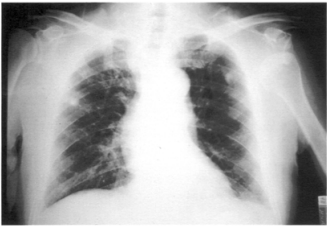

23 67 歲男性養了一隻西藏獒犬,某日遛狗時,獒犬突然狂奔,將老先生拉倒在地,導致左肩疼痛,左 臂上舉困難。老先生經送醫檢查發現,其 X 光片如下圖所示,其正確診斷應為下列何者?

(A)肩關節脫位 (B)鎖骨骨折 (C)肱骨頸骨折 (D)肩鎖關節脫位